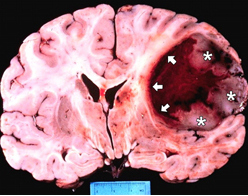

Çoğunlukla beyin omurilik sıvı akış yolunun bloke olması sonucu beyinde aşırı miktarda sıvı artışının olduğu durumlarda hidrosefali denilen klinik tablo meydana gelir. Bu aşırı miktardaki sıvı artışı, çevre beyin dokusuna bası yaparak zarar görmesine neden olmaktadır. Tedavi edilmediği durumlarda ölümcül olabilmektedir. Hastalığın belirtileri yaşa göre değişmektedir.

Beynimiz jelatin kıvamında bir dokudur ve beyin omurilik sıvısının içinde adeta yüzmektedir. Bu sıvı ayrıca beynin derininde yer alan ventrikül adı verilen boşlukları doldurmaktadır. Böylece beyin sarsıntıdan etkilenmez ve beyin omurilik sıvısı içinde batmaz bir şekilde yüzmektedir.

Beyin omurilik sıvısının üretim, akım ve emilim süreci arasındaki varolan hassas denge, sıvının kafa içerisinde normal basınç altında devirdaim yapabilmesi açısından çok önemlidir. İşte hidrosefali denilen klinik tablo bu hassas dengenin bozulması durumunda ortaya çıkar. Örneğin ventriküller arasında geçişi sağlayan kanalların daralması veya sıvının emilmesinde bir hasar olması gibi sıvının devirdaimi sürecinde herhangi bir basamakta aksama olması hidrosefali oluşumuna neden olmaktadır.